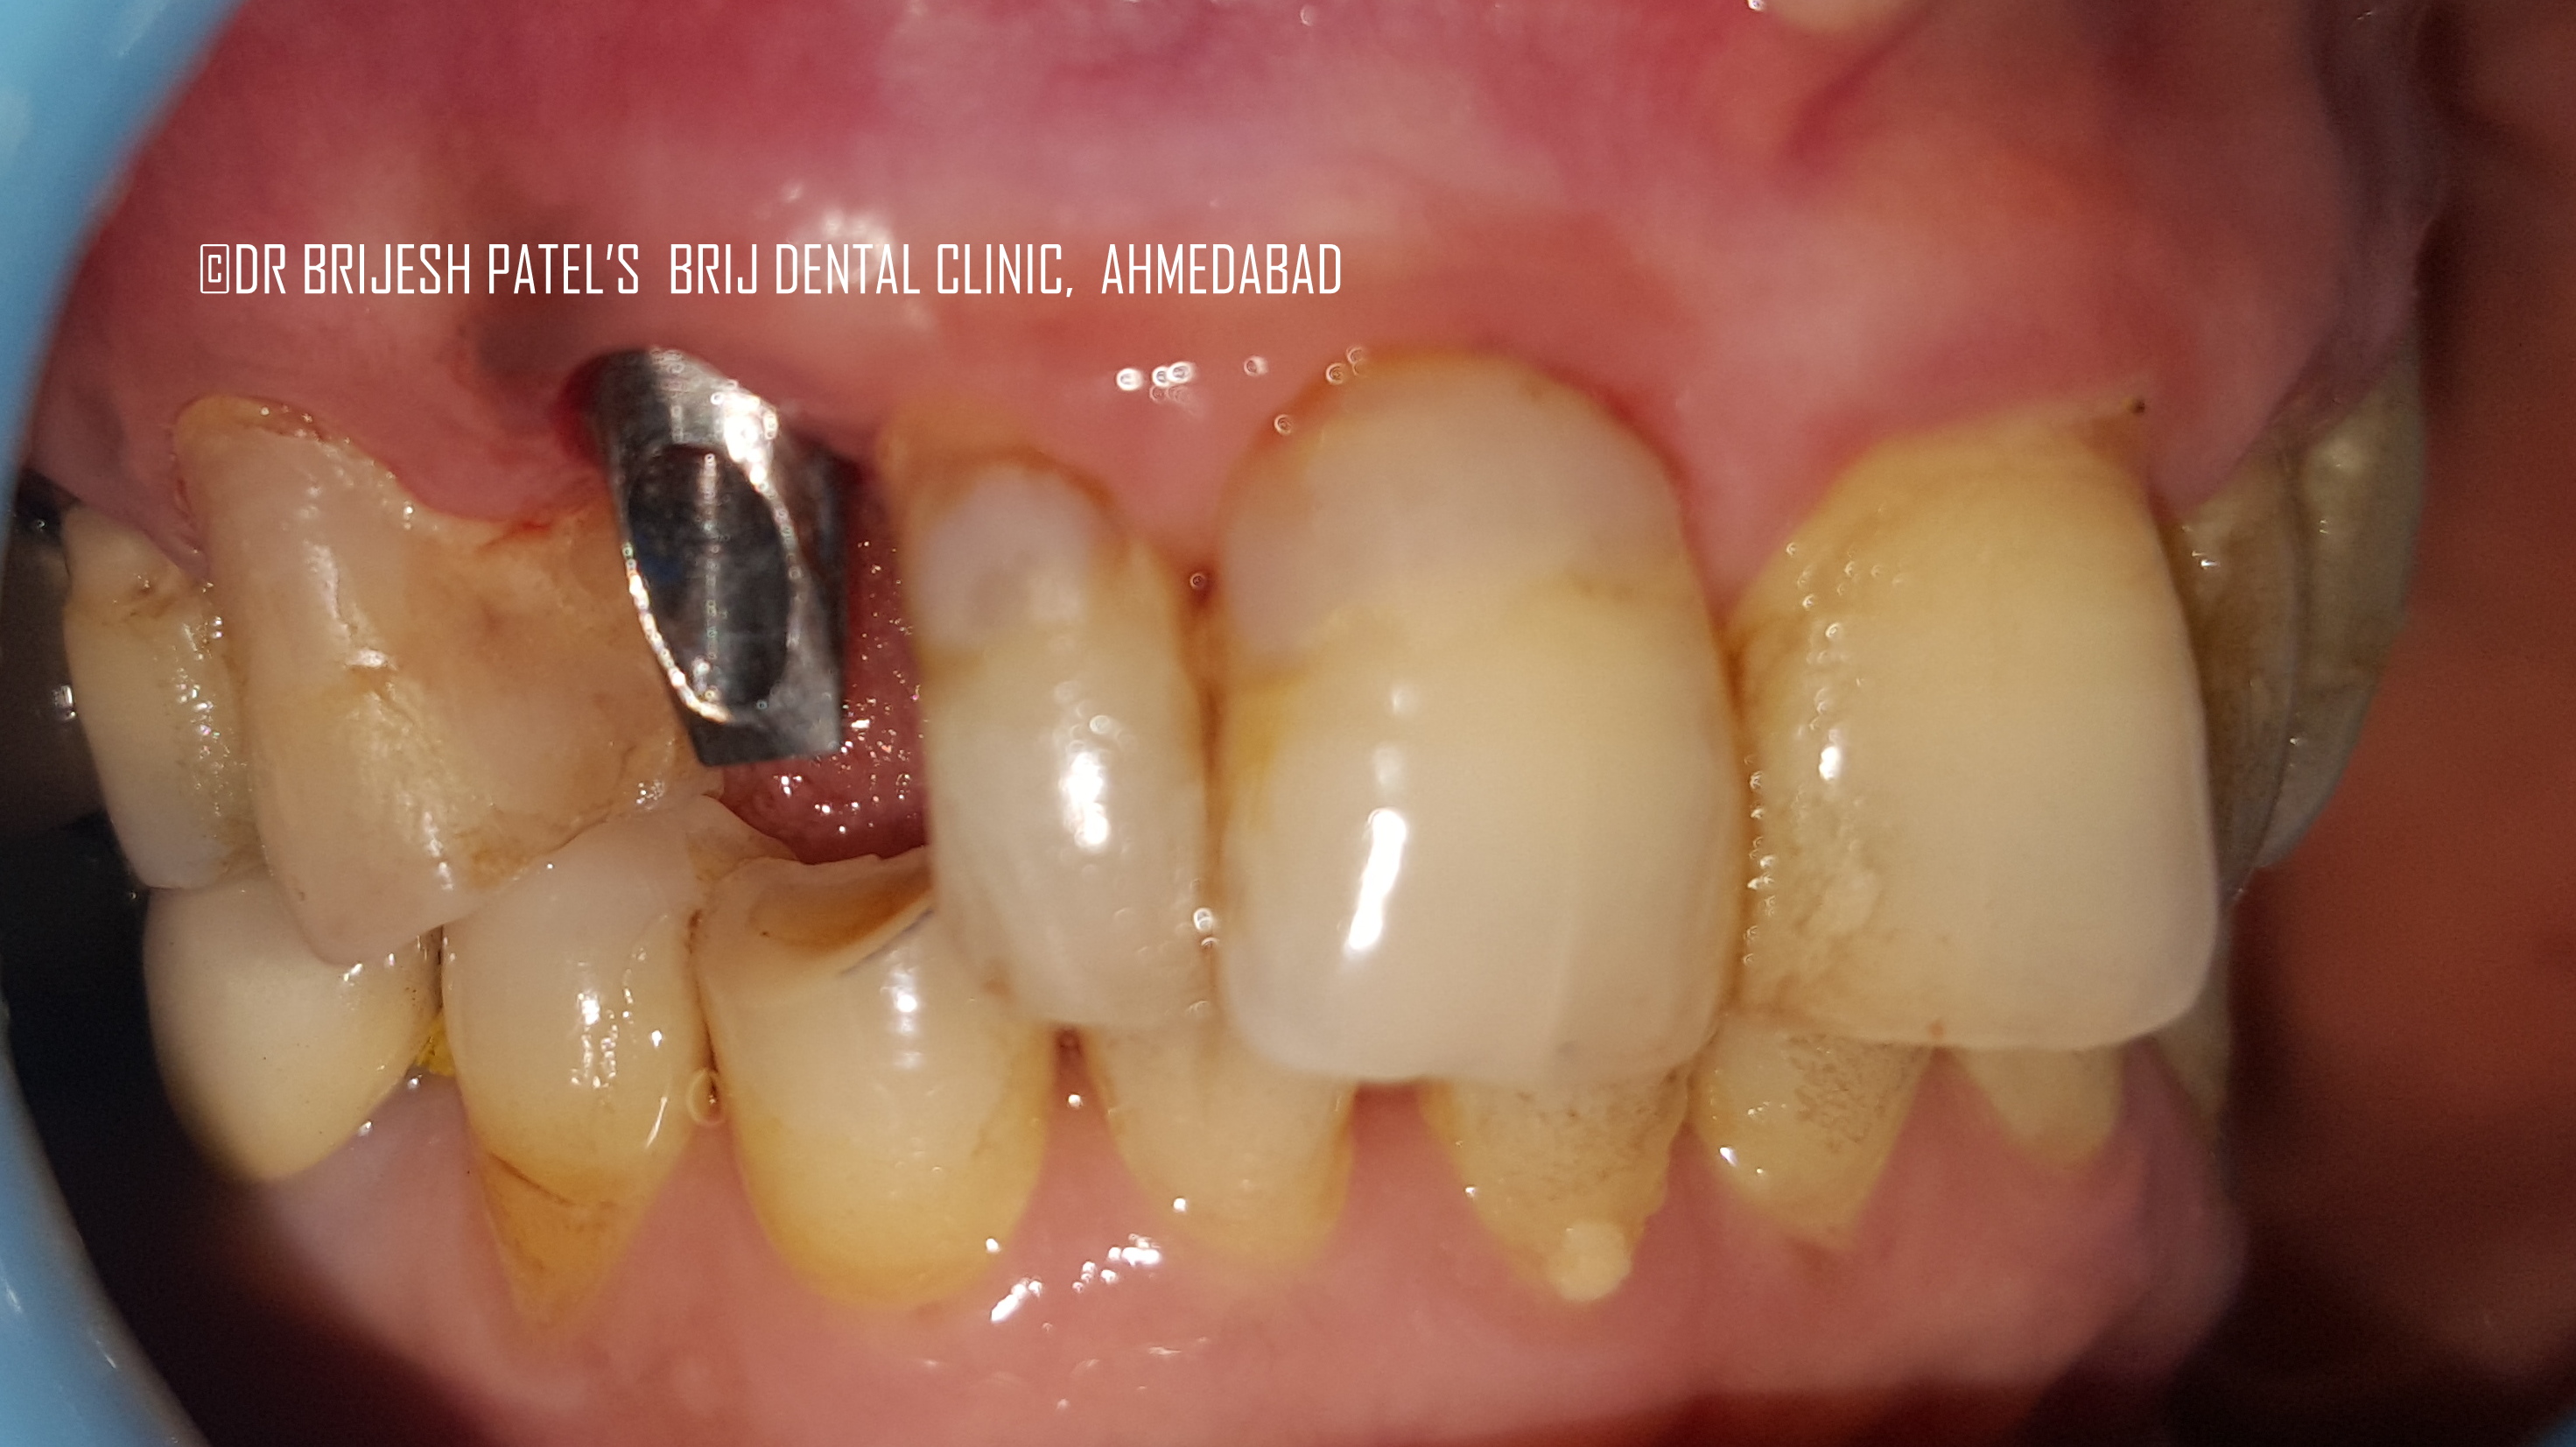

From www.brijdentalclinic.com

Cost of Dental Implants Ahmedabad India Best Dental Implant Clinic Cuspid Tooth Implant If a cuspid tooth gets impacted, every effort is made to get it to erupt into its proper position. In this post, we’ll explain how impacted cuspids surgery works and why early detection is key to successful outcomes. Problems with human canine teeth can range greatly, from pain and discomfort due. The most common teeth to become impacted are your. Cuspid Tooth Implant.